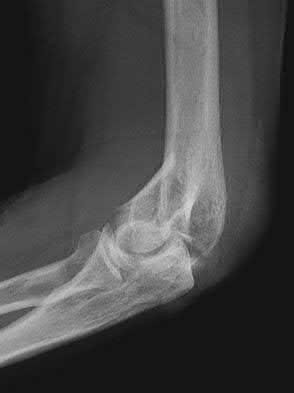

1020) Figures 108a through 108c are the radiographs of a 38-year-old man who fell on an outstretched hand 1 week ago and now reports severe left elbow pain. Examination of the wrist reveals normal range of motion with no tenderness or swelling. Pain limits examination of his elbow. What is the most appropriate management to determine if surgery is indicated?

5. Intra-articular lidocaine injection followed by repeat examination Corrent answer: 5

Whereas there is controversy regarding the best treatment for comminuted radial head fractures, nondisplaced and minimally displaced fractures in which there is no block to motion can be treated nonsurgically. At the time of initial examination, it is important to determine that there is no block to range of motion. If pain limits the ability to examine the patient's range of motion, local analgesia with intra-articular lidocaine is most appropriate. Whereas general anesthesia would be useful for open reduction and internal fixation, the necessity for open reduction and internal fixation is best determined first before scheduling surgery. Neither a CT or MRI scan is necessary if the patient has no block to range of motion. Early range of motion is the best treatment for radial head fractures treated nonsurgically. After immobilization for 2 weeks, it may be difficult to determine whether there is a block to motion because the patient will likely have decreased elbow pronation and supination.